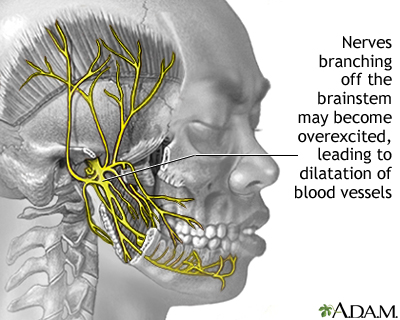

A migraine headache is caused by abnormal brain activity. This activity can be triggered by many things. But the exact chain of events remains unclear. Most medical experts believe the attack begins in the brain and involves nerve pathways and chemicals. The changes affect blood flow in the brain and surrounding tissues.

Migraine headache - illustration

Migraine headache

illustration

Migraine headache - illustration

Migraine headache

illustration